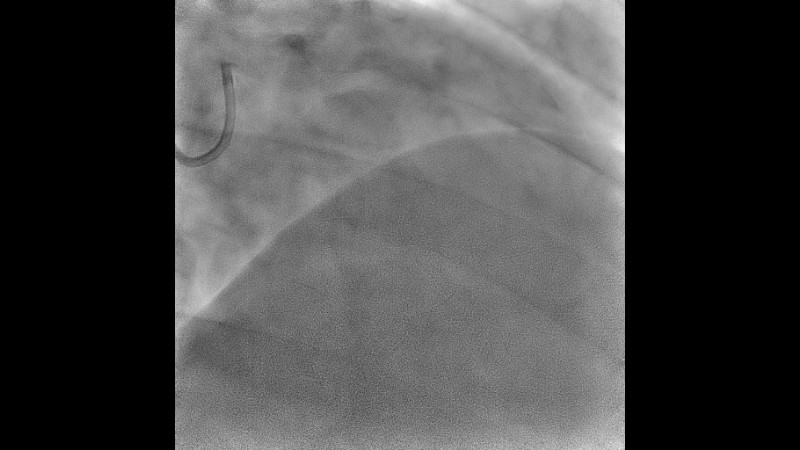

Explore the management of heavily calcified LAD lesions in this PCRGulf-GIM 2025 session. Discover how OCT imaging guides lesion assessment, differentiates superficial from deep calcium, and informs the need for plaque modification. Learn when and how to use orbital atherectomy or intravascular lithotripsy, and follow the step-by-step stent implantation, optimisation, and final evaluation using both angiography and OCT.